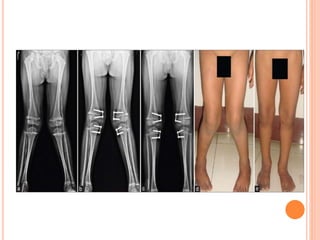

OPERATIVE

 hemiepiphysiodesis or physeal tethering

(staples, screws, or plate/screws) of medial side

 indications

 > 15-20° of valgus in a patient <10 years of age

 if line drawn from center of femoral head to center

of ankle falls in lateral quadrant of tibial plateau in

patient > 10 yrs of age

 If lateral portion of epiphyseal plate is intact as seen

in the radiographs, it contributes to the longitudinal

growth at a reduced rate.

 This situation is suitable for stapling of the medial

epiphysis, which arrests the growth on the medial

side, allows the growth on the lateral side, and thus

helps to correct the deformity

 to avoid physeal injury place them extraperiosteally

 to avoid overcorrection follow patients often

 growth begins within 24 months after removal of

the tether